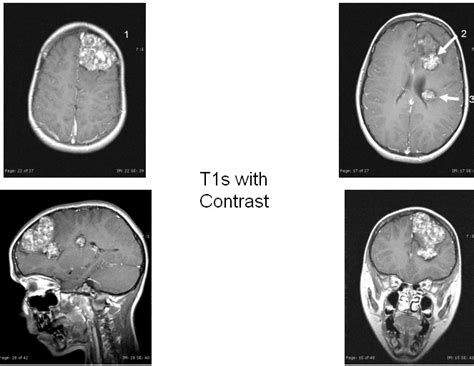

15 + Corona Radiata Lesions Background Images. Lesions seated inferiorly are likely to correlate with poorer. Data suggests that the corona radiata and superior capsular lesions may correlate with more favorable levels of functional recovery.

Figure 1:Mills’ syndrome: case report- Open-i